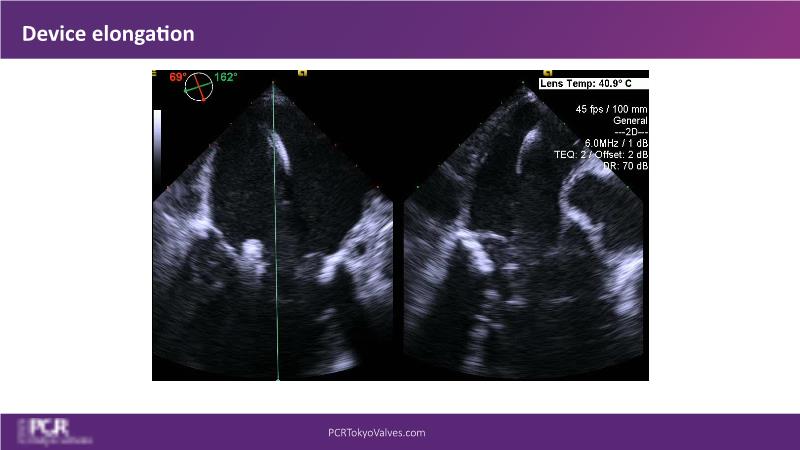

Watch this session to get an overview of a new TEER device, follow the step-by-step procedure related to initial experiences with this device for a Japanese patient with degenerative mitral regurgitation, learn about the latest data from RCT and registries, and follow discussions of challenging TEER cases!

- To understand how novel TEER device provides new possibilities in TEER

- To learn procedural step-by-step of novel device